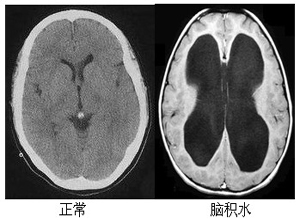

人腦是浸在“水”中的,這種“水”就是腦脊液。腦脊液包圍并支持著整個腦及脊髓。腦脊液是可以流動的,但如果因腦出血、外傷或感染等原因導致腦脊液循環(huán)受阻或吸收障礙,腦脊液在腦室蓄積過多,就會導致腦積水。那么腦積水不治會影響壽命嗎?